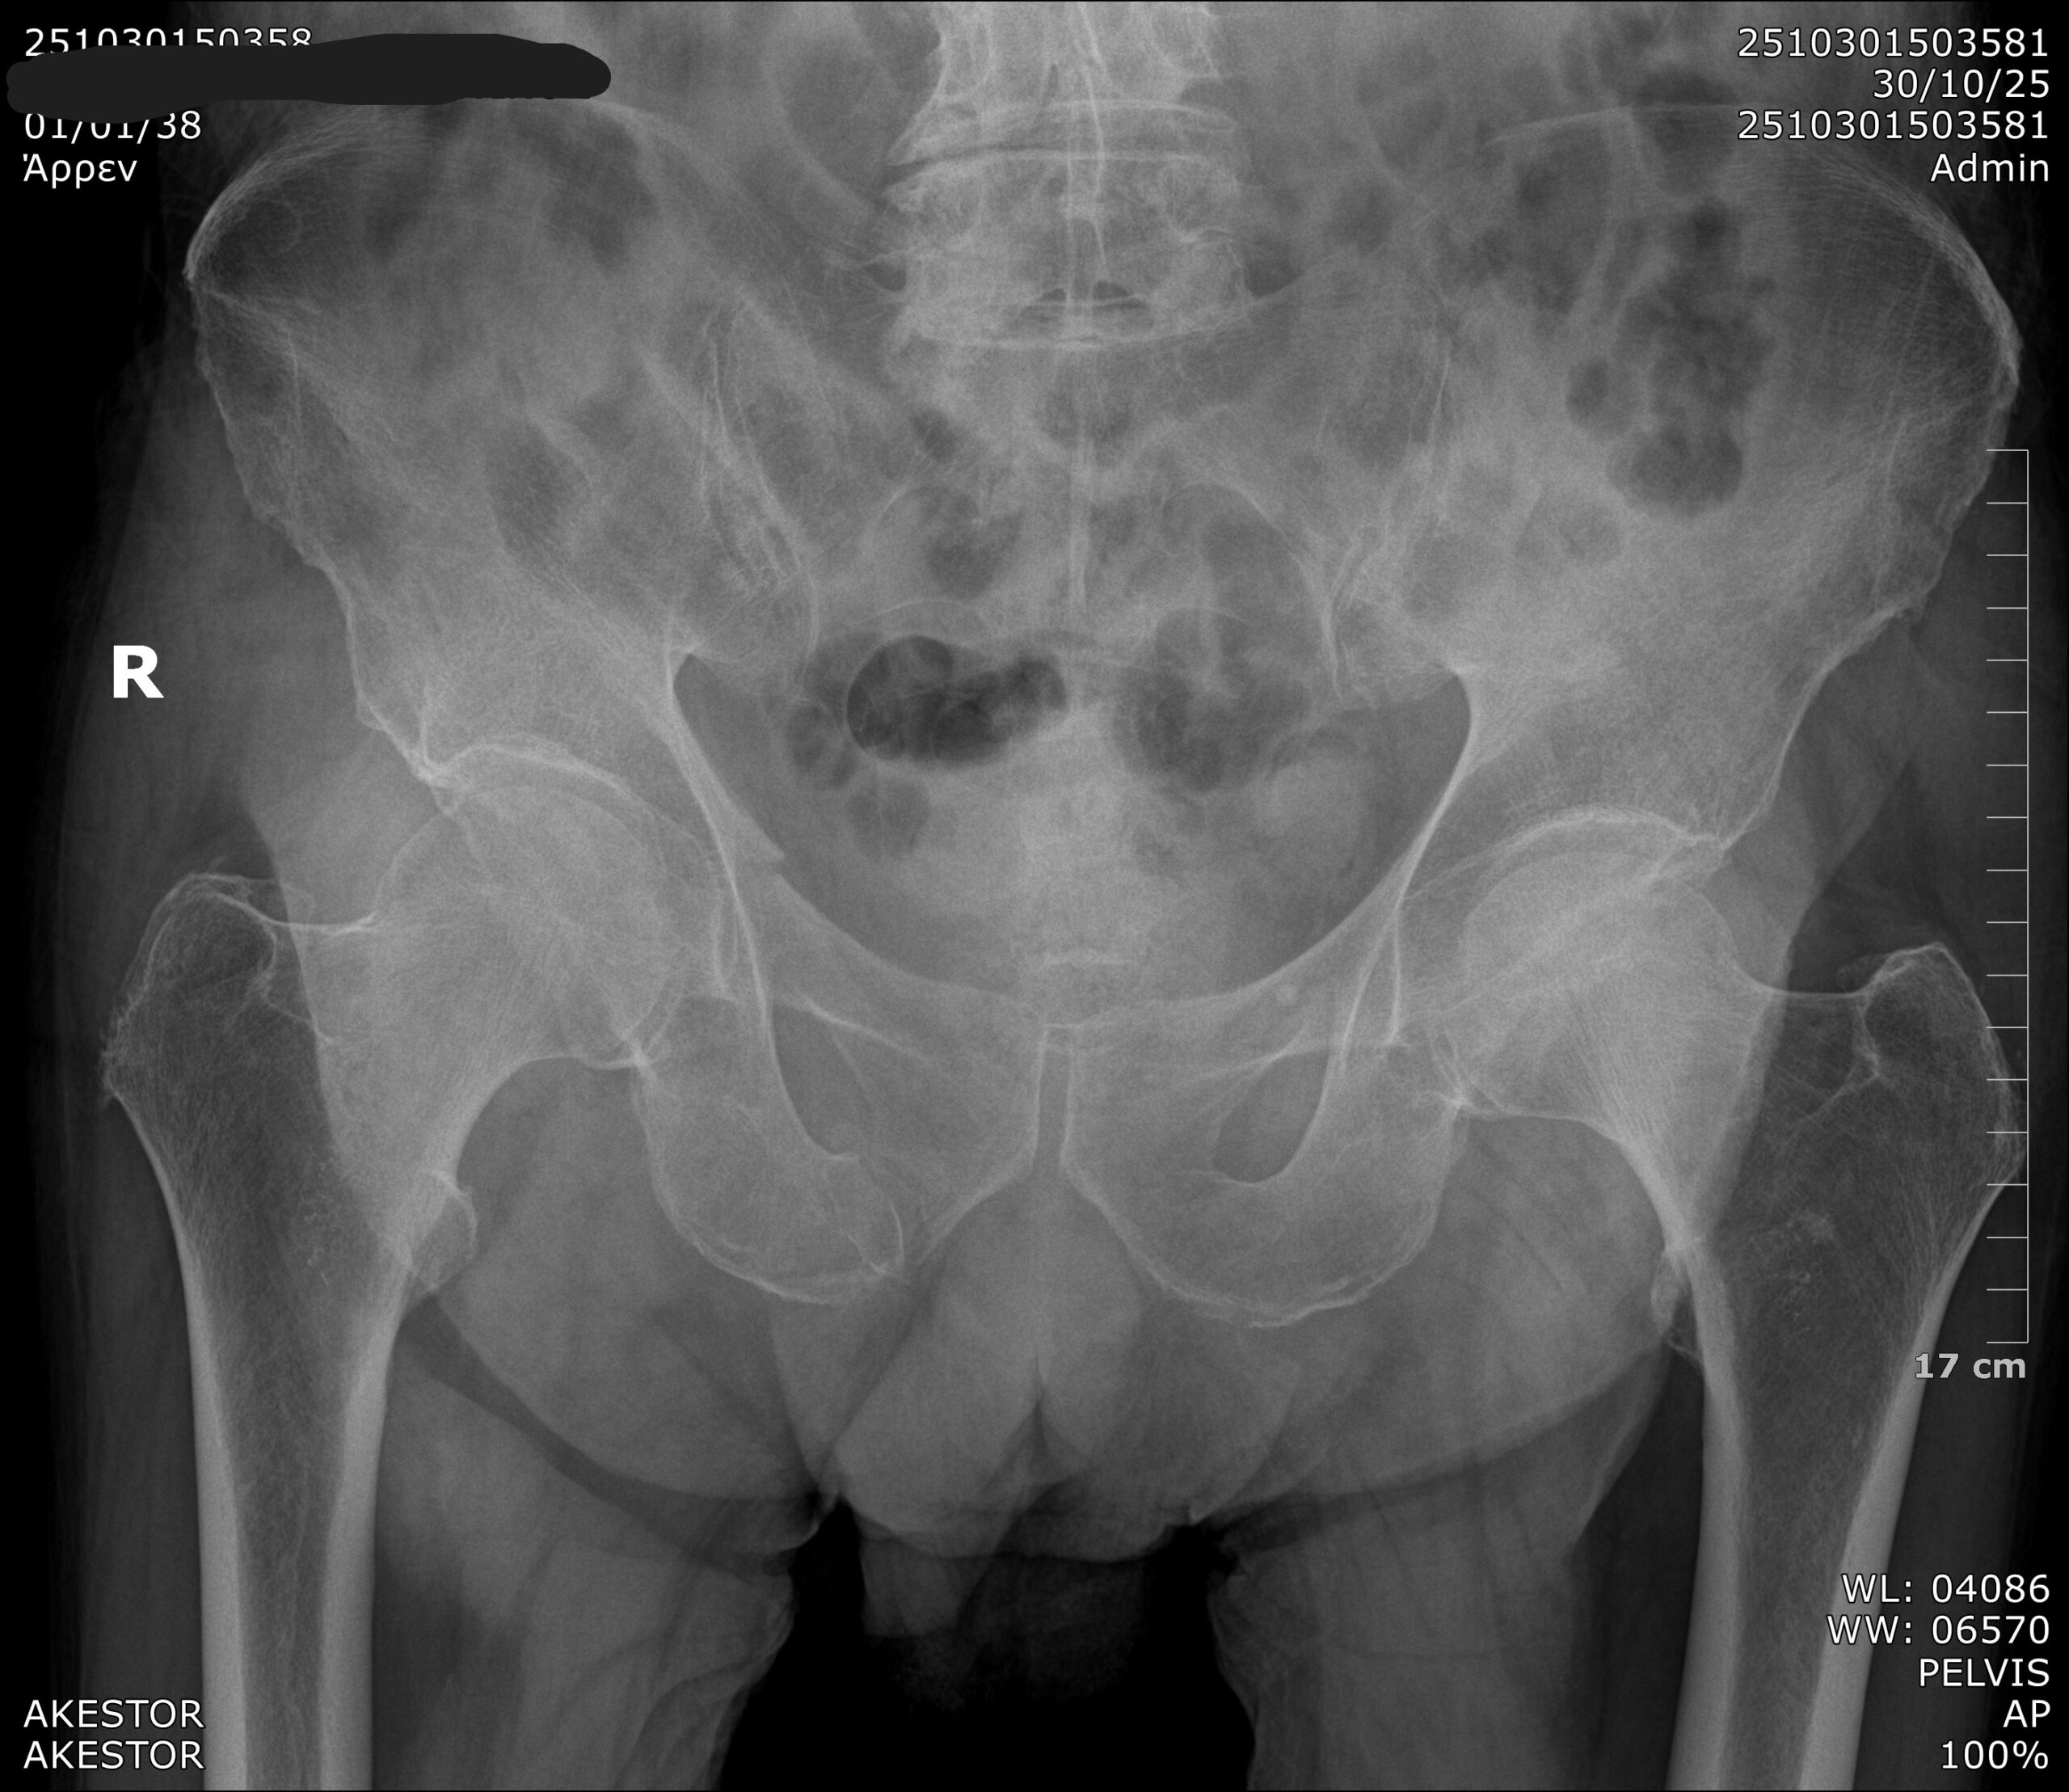

Ακτινογραφία στο Σπίτι: 100% Ψηφιακή Απεικόνιση Υψηλής Ευκρίνειας

Όλες οι ακτινογραφίες κατ’ οίκον πραγματοποιούνται με πλήρως ψηφιακή τεχνολογία, όχι απλώς ψηφιοποιημένες εικόνες. Η διαδικασία γίνεται με τελευταίας γενιάς εξοπλισμό, που περιλαμβάνει ακτινολογικές λυχνίες και flat panel detectors κορυφαίων κατασκευαστών, εξασφαλίζοντας μέγιστη ακρίβεια και καθαρότητα στην απεικόνιση.

Η ψηφιακή ακτινογραφία προβάλλεται άμεσα στον χώρο του ασθενούς και τα αποτελέσματα αποστέλλονται ηλεκτρονικά στον θεράποντα ιατρό για άμεση αξιολόγηση.

Σε σχέση με την παραδοσιακή ή ψηφιοποιημένη μέθοδο, η ψηφιακή τεχνολογία προσφέρει ανώτερη ευκρίνεια, ταχύτερη διάγνωση και μειωμένη ακτινοβολία, αποτελώντας την ιδανική επιλογή για εξετάσεις κατ’ οίκον.

Η ακτινογραφία στο σπίτι πραγματοποιείται αποκλειστικά με 100% ψηφιακή τεχνολογία υψηλής ευκρίνειας, προσφέροντας άμεσα και αξιόπιστα αποτελέσματα. Με τη χρήση σύγχρονου εξοπλισμού, όπως ακτινολογικές λυχνίες και flat panel detectors τελευταίας γενιάς, εξασφαλίζεται άριστη ποιότητα εικόνας και χαμηλότερη ακτινοβολία σε σχέση με τις ψηφιοποιημένες μεθόδους. Η εικόνα εμφανίζεται άμεσα στον χώρο του ασθενούς και αποστέλλεται ηλεκτρονικά στον θεράποντα ιατρό για άμεση αξιολόγηση.